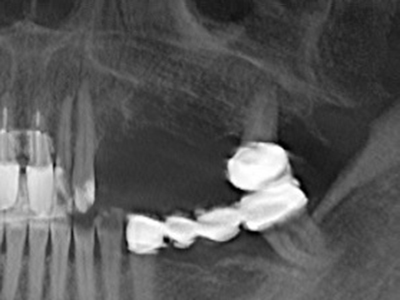

Фиг. 1: Препарация на костно покритие с Piezomed (W&H Залцбург, Австрия).

Фиг. 2: Хоризонтален и вертикален латерално-максиларен дефект с висока линия на усмивката с индикация за пре-реконструкция за имплант.

Фиг. 3: Базалното разделяне на блока е по-лесно със специалните извити накрайници.

Фиг. 4: Допълнителни автогенни костни стърготини се събират със скалер за кост.

Фиг. 5: Проверка на размера на блока към страната на реципиента.

Фиг. 6: След препарация на мукопериосталната клапа.

Фиг. 7: Първоначалната препарация на мукозната мембрана на синуса може да бъде извършена с ултразвук.

Фиг. 8: След синус лифт, кресталната костна шина е фиксирана към дефектния алвеоларен гребен.

Фиг. 9. Запълване с животински костозаместител (Cerabone 0.5–1 mm, Botiss Bio-materials, Berlin) и автогенна кост (палатинален изглед).

Фиг. 10: Покритие на аугментираната зона с дълготрайна стабилизираща перикардна мембрана (Jason collagen membrane, Botiss).

Фиг. 11: Следоперативната панорамна снимка показва вертикалната аугментация и синус лифта.

Фиг. 12: След шест месеца на заздравяване, алвеоларният гребен е добре оразмерен триизмерно.